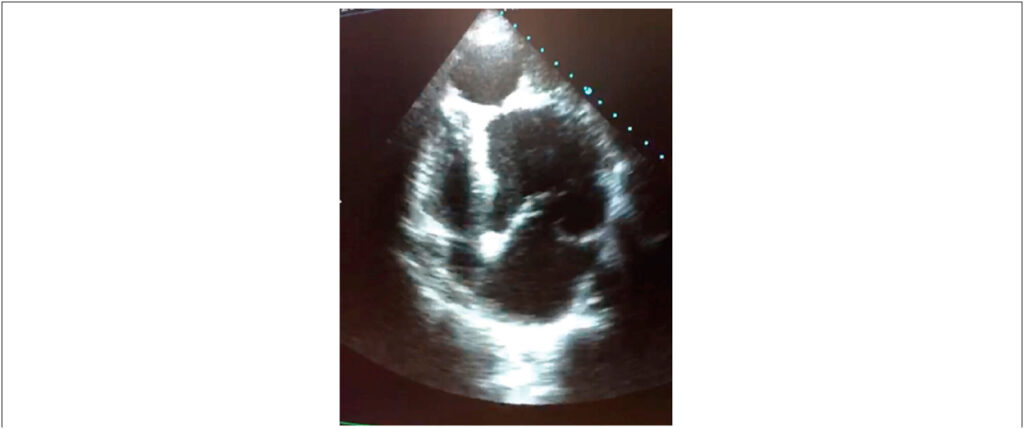

Figure 1

Echocardiography image in apical four-chamber view showing an apical pseudoaneurysm.